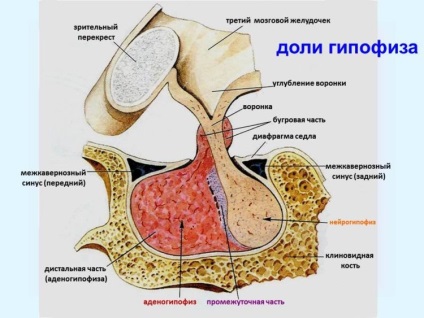

Szerkezetét. Különbséget tenni a két agyalapi. Elülső lebeny körülbelül hét tized teljes mérete az agyalapi mirigy. Ez van kialakítva nagy sűrűségű mirigyszövetekben. Töredék áthalad nagyszámú ereket. Itt van, hogy hormonokat termelnek.

Hátsó részesedése hipofízis szövetekben képződött, hasonló a tulajdonságait, hogy az idegrendszer. Nincs hormonok termelését. Hátulsó lebenye „működik” partner agyi idegi központja - a hipotalamuszban. Ez a rész az agy termel hormonokat oxitocin és a vazopresszin. majd elküldi őket a hátsó lebeny az agyalapi mirigy - a szó szoros értelmében a betét.

Még hormonok, amelyeket nem termeli az agyalapi mirigy. de csak tárolt vissza a részvény, amely az úgynevezett neurohypophysis. A vazopresszin szabályozza a víz és a só csere, ha szükséges, ő is ad jelet érszűkület. Az oxitocin serkenti a tejtermelést szoptató anyáknak. valamint a post-partum méhösszehúzódások.